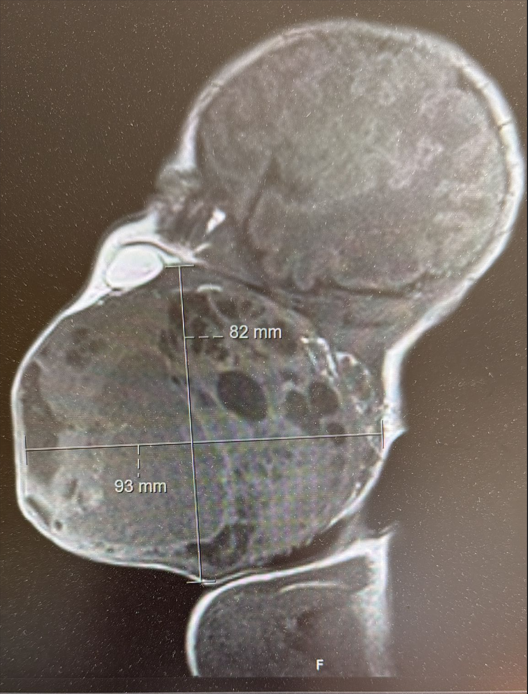

Prema nalazima magnetske rezonancije prije poroda, tumor je bio gotovo veličine djetetove glave i zatvarao je dišne puteve. Dijete bi bilo životno ugroženo ako bi se rodilo normalnim putem, stoga je tim liječnika morao razraditi i biti spreman na nekoliko varijanti liječenja, a na kraju je profunkcionirala prva opcija.